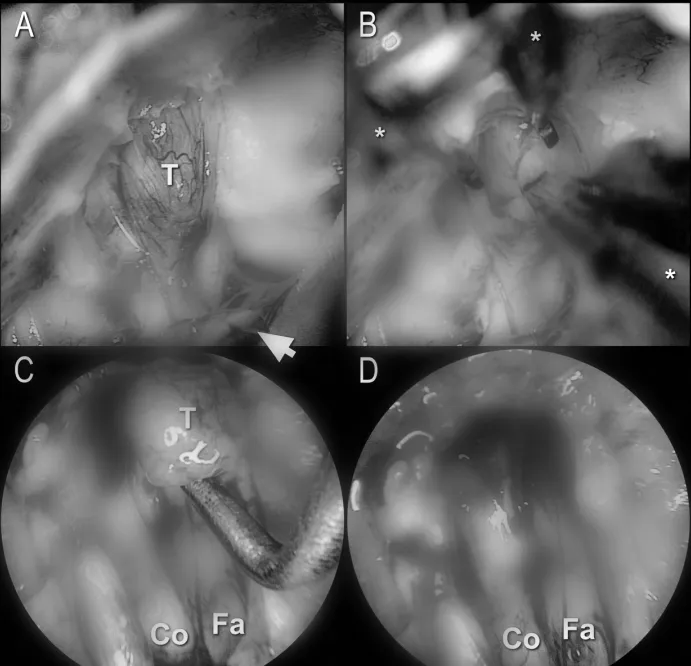

图2. 左侧听神经瘤的切除:显微镜下内听道开放后显露的内听道内肿瘤(A)。请注意吸引刮匙的尖端(箭头所指)。在持续冲洗下,通过牵引-反牵引技术对肿瘤进行双器械分离切除(B)。在内窥镜视下分离内听道底部的残余肿瘤(C)。使用45度内窥镜进行最终检查显示无肿瘤残留(D)。Co = 耳蜗神经;Fa = 面神经;T = 肿瘤;* = 镊子

图1. 吸引刮匙:该器械有不同的尺寸(A)。注意其头端的开孔(B)。手术中,刮匙被放置于手术野的下方,位于小脑表面(C);图中所示为左侧手术。T = 肿瘤